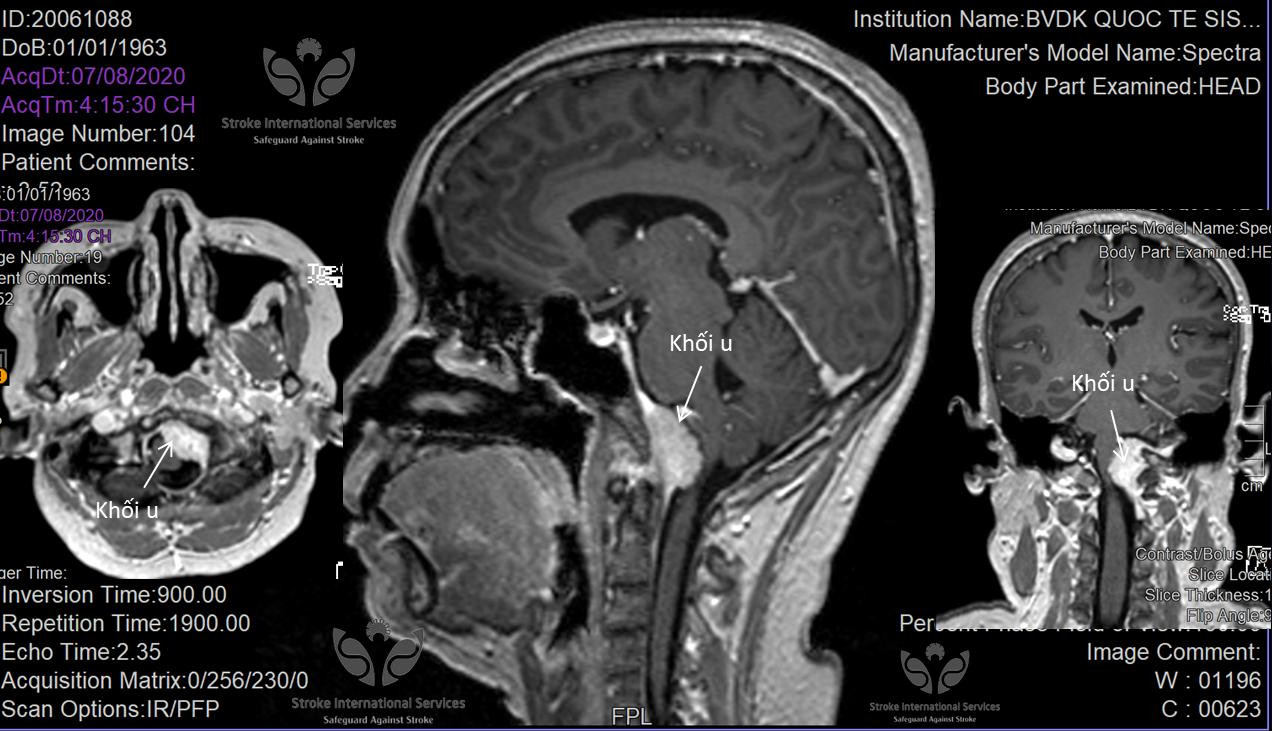

Kết quả chụp MRI 3 Tesla của bệnh nhân- ảnh: BVCC

Tại đây, bà N. được bác sĩ chỉ định chụp MRI 3 Tesla để tìm nguyên nhân. Kết quả cho thấy, bà N. bị u màng não vùng mặt dốc xương đá - lỗ chẩm rất hiếm gặp.

Tuy nhiên, để không bỏ sót bệnh lý chúng tôi đã cho bệnh nhân tầm soát bằng những phương tiện chẩn đoán hình ảnh kỹ thuật cao, phát hiện ra u màng não ở vị trí rất hiếm gặp, rất khó chẩn đoán. Nếu bệnh nhân này chỉ định chụp CT có thể không phát hiện được khối u, nếu khối u này lớn thêm bệnh nhân có thể bị yếu liệt tứ chi do chèn ép hành não”.